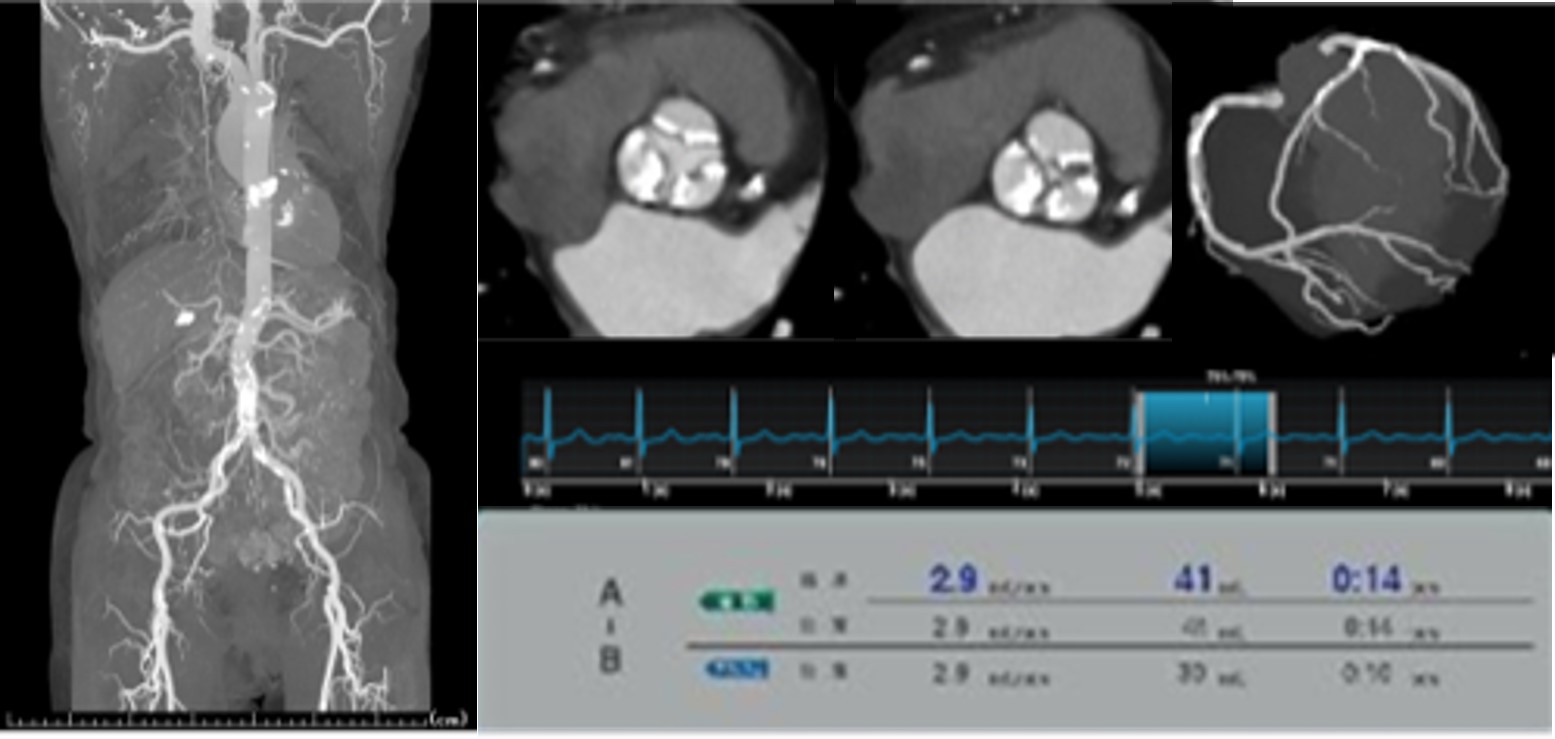

心臓CTA造影剤低減

心臓CTAに関して2021年6月1日から除脂肪体重60㎏以下の場合、撮影管電圧を100kVpへ下げ、体重当たりのヨウド量設定を24.5㎎I/㎏/secから21.0㎎I/㎏/secへ減量しました。さらなる造影剤低減指示に対しては、注入時間を12秒から10秒へ短縮し対応しています。TAVI術前検査においても21.0㎎I/㎏/secへの減量で検査可能となりました。(fig4)

RevolutionCT_Nishioshimin06.jpg

Fig4. 造影剤減量指示のTAVI術前検査

Revolution CT導入前後での造影剤使用量比較を表します。平均使用量が大きく引き下げられました。(fig5)

これにより、現在取り扱いのない少量シリンジのニーズが生まれ、造影剤を再検討することで入院時造影剤コスト抑制を効率的に行えることが示唆されました。